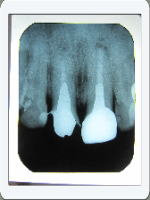

これも症例1と同じです。黒い影が2つ消えています。

もし歯を抜いていたらブリッジか入れ歯になっています。

患者様の口腔の健康の維持に貢献できたと歯科医としての

喜びに尽きる症例です。